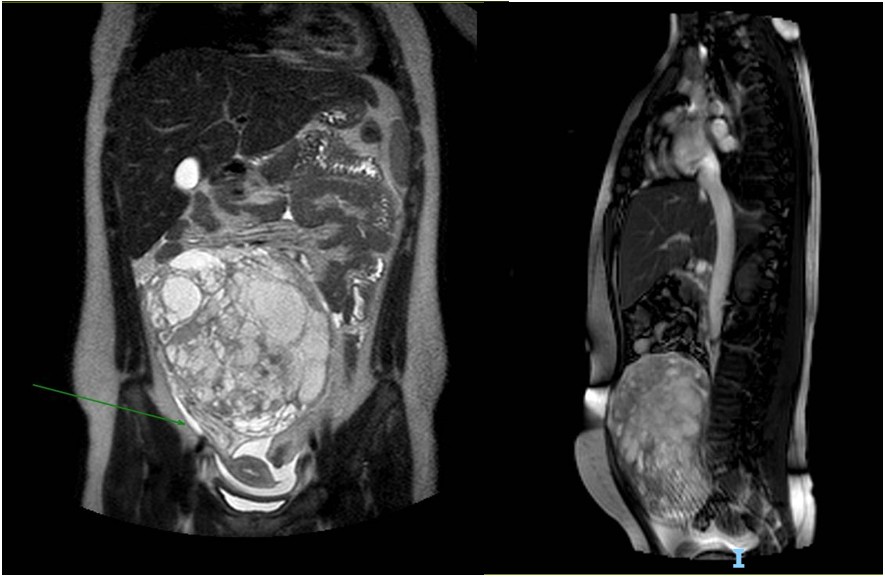

Se solicita RM de pelvis con contraste que evidencia formación tumoral abdomino-pelviana central en íntimo contacto con el peritoneo sin claro plano de clivaje con el mismo. La misma presenta bordes bien definidos de intensidad heterogénea multiquística con tabiques y realce heterogéneo con contraste. Se identifican áreas de restricción en difusión. Mide: 14.4 x 7.4 x 14,2 cm (ver imagen 2). La imagen impresiona en relación al anexo derecho. Se evidencia dilatación urétero-pielocalicial derecho.

Imagen 2. Resonancia magnética. Cortes coronal y sagital en t2. Se identifica formación tumoral abdominopelviana central en íntimo contacto con el peritoneo sin claro plano de clivaje con el mismo. La misma es ovoidea de bordes bien definidos de intensidad heterogénea multiquística con tabiques y realce heterogéneo con contraste. Mide: 14.4 x 7.4 x 14,2 cm que podría corresponder a tumor de estirpe moderado a agresivo con componentes seroso-mixto.